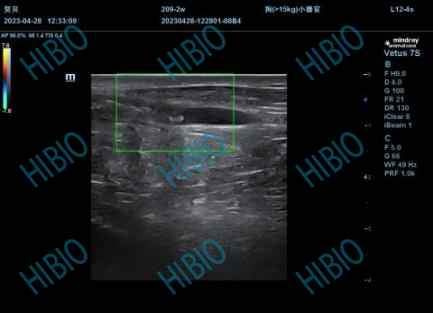

外科手术是一部从残酷到规范的人类探索史,其中伤口护理的技术更迭也随着现代医学的发展而逐步人性化。 近年来,患者市场对手术服务质量的要求不断提高,传统的手术缝合方法存在诸多局限,已无法满足临床需求。随着生物医用材料技术的更新,吻合夹、电凝、封堵、止血剂等技术不断被开发问世,医用粘合剂成为重要产品之一。医用粘合剂可将破裂或切开的人体组织进行粘合,无需缝合伤口且不会造成体液渗漏。医用粘合剂种类较多,纤维蛋白胶、α-氰基丙烯酸酯是主要产品类型。 α-氰基丙烯酸酯类医用粘合剂属于三类医疗器械,在申报注册时要严格遵循其相关指导原则。关于临床前动物实验部分,指导原则明确申请人应提供申报产品的动物试验资料。建议根据产品预期用途在适合的动物模型中进行器械的性能特性评价。这些试验应能代表产品用于临床的使用方法,应对动物试验中粘合剂的用量和产品临床用量进行对比,还应提供对动物模型选择依据和限制的论证。例如,用于体表切口的局部封闭时,建议可选择小型猪模型。试验应对炎症反应、正常愈合以及延迟愈合、伤口开裂、组织不良反应和感染等情况进行评价,并视情况评价其组织病理学。动物试验应与产品临床使用部位和使用方法相适应,包括以下内容: 模型选择的依据 试验中使用的治疗参数[如:使用方法(点状粘合或薄层喷涂)、使用剂量等]与建议用于人体的治疗参数的比较 试验方案和方法 若已有同类产品上市,建议选择同类已上市产品作对照。 结果(包括各项研究的原始数据) 结论 杭州赫贝科技有限公司(以下简称赫贝)与多个企业合作,严格按照产品指导原则,开发了α-氰基丙烯酸酯类医用粘合剂类医疗器械产品的体内验证方法,通过检测粘合剂粘合即刻血管闭合情况、粘合剂对粘合血管的炎症反应和纤维化程度以及血管六个月内是否再通评估产品有效性,通过评估粘合剂脱落、血管周围组织炎症反应以及纤维化程度等风险对产品安全性进行评估。共同开发验证α-氰基丙烯酸酯类医用粘合剂类医疗器械的安全有效性。以下为相关合作案例展示 实验目的:利用山羊大隐静脉的天然组织学和结构特点,通过使用α-氰基丙烯酸正丁酯静脉粘合系统将实验用山羊的大隐静脉进行闭合,以此对α-氰基丙烯酸正丁酯静脉粘合系统的进行安全性及有效性进行评估。 实验动物:山羊 检测指标:动物大体观察、隐静脉HE染色、隐静脉Masson染色、血液学检查。 实验结论:试验表明通过使用α-氰基丙烯酸正丁酯静脉粘合系统将实验用山羊的大隐静脉进行闭合使用中是安全有效的。 发自小木虫Android客户端 |